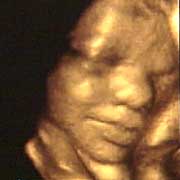

圖文:胎兒子宮內(nèi)表情豐富 專家稱提供研究新依據(jù)

中新網(wǎng)9月13日電 英國(guó)天空新聞報(bào)道,英國(guó)科學(xué)家圖亞特·坎貝爾最近利用先進(jìn)的掃描技術(shù)清晰地拍下了孕婦子宮中胎兒的表情,透過(guò)他拍攝的照片,人們可以清楚的看到一個(gè)尚未降臨世間的小生命喜、怒、哀、樂(lè)的表情。

斯圖亞特.坎貝爾是倫敦著名的產(chǎn)科教授,他利用超聲掃描技術(shù)拍攝到了胎兒在子宮中打呵欠、眨眼、吮手指、哭泣甚至微笑的畫面,這些都為胎兒行為的研究提供了新的依據(jù),專家認(rèn)為,這一突破將推動(dòng)?jì)雰航】悼茖W(xué)的發(fā)展,包括對(duì)唐氏綜合癥等嬰幼兒疾病的診治將起到極大的推動(dòng)作用。

此前,醫(yī)學(xué)界一直認(rèn)為,嬰兒要到降生后才可以做出喜、怒、哀、樂(lè)的表情,要通過(guò)模仿母親才可以學(xué)會(huì)微笑。

坎貝爾教授說(shuō):“有個(gè)這種技術(shù),現(xiàn)在許多問(wèn)題都可以進(jìn)行研究了。比如說(shuō),患有唐氏綜合癥的嬰兒和正常嬰兒的活動(dòng)方式是否一樣?胎兒是否因?yàn)楦吲d才笑?胎兒哭是否是因?yàn)樵谧訉m中受到打擾?既然我們都認(rèn)為子宮內(nèi)是一片黑暗,那胎兒為什么會(huì)眨眼呢?”(章田)